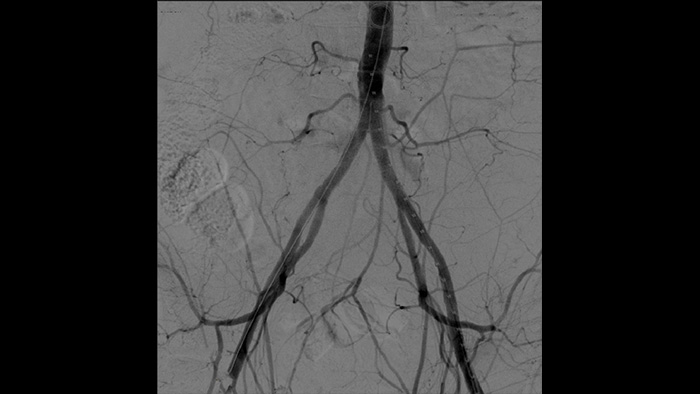

À l’aide de l’arceau mobile Philips Zenition, le docteur Vila obtient des images de haute qualité qui lui permettent d’effectuer la plupart des procédures vasculaires à faible dose.

Grâce au système Zenition, la qualité des images en angiographie par soustraction numérique s’est considérablement améliorée. Nous ne voyons plus d’image granuleuse. Nous voyons une image très claire."

L’angiographie par soustraction numérique (ASN) est utilisée dans les procédures vasculaires interventionnelles pour visualiser clairement les vaisseaux sanguins en retirant les structures qui peuvent masquer la visibilité des vaisseaux. Le guidage fluoroscopique superpose une image de contraste soustraite acquise précédemment sur la fluoroscopie en temps réel, ce qui vous permet de suivre un appareil sans réinjecter de produit de contraste.